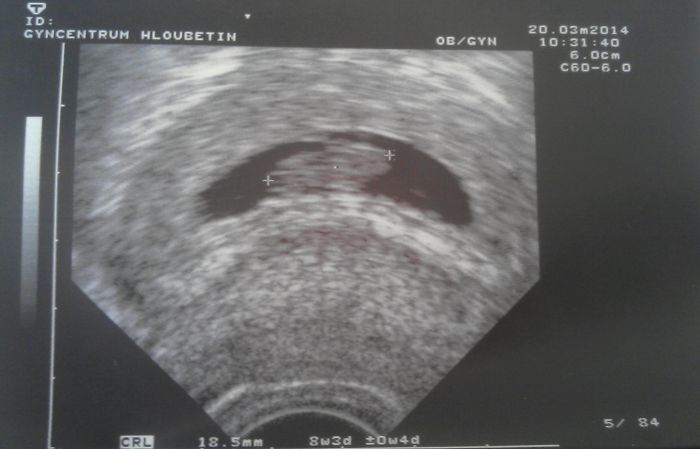

Holky dnesni kontrola v poradku, mam misto 9+3 - 8+3...

mimisek s sebou hazel, takze byl doslova porod neco vyfotit a zmerit

prikladam foto

...tak fotka není úplně kvalitní, fotila jsem si monitor, ale vidět je i když je to prďolka

Jinak, mě teda ještě krev na nic nebraly, prý mě tím teď ještě nebudou zatěžovat, mimi je tam kde má být, srdíčko je taky tak asi proto.

Miško, moc pěkné, roste jak z vody

taky mám skoro o týden míň, ale to nevadí, třeba to příště bude ještě jinak, taky mi říkal, že ho nemohl změřit...